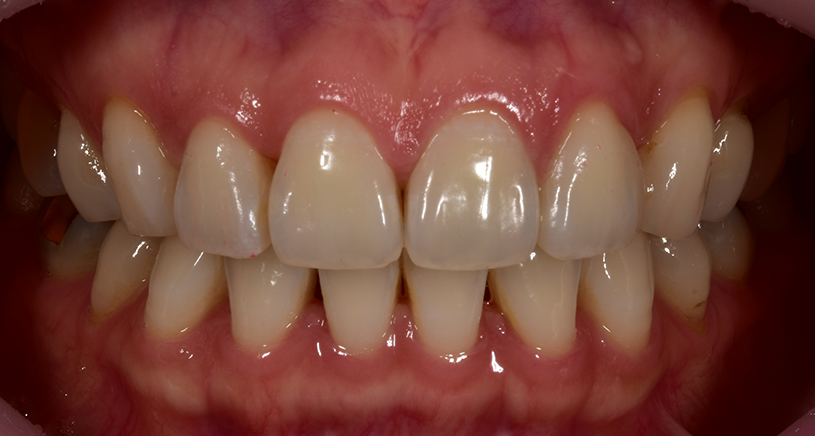

< 사례 1 >

블랙트라이앵글 무삭제라미네이트 <블랙필름> 치료 전

블랙트라이앵글 무삭제라미네이트 <블랙필름> 치료 후